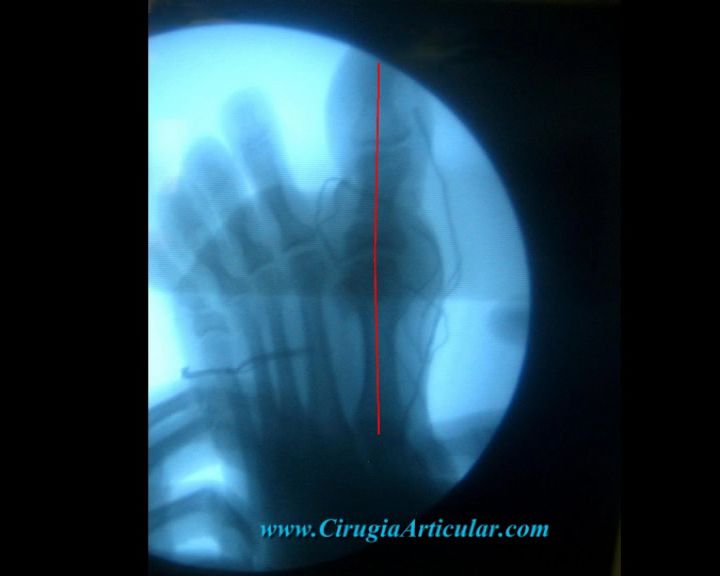

Foto 4

En esta radiografía podemos ver la deformidad de primer dedo con respecto al pie que se evidencia con la línea roja que sigue el eje de los dedos. En condiciones normales debería ser una línea más o menos recta. En este caso vemos como describe un ángulo